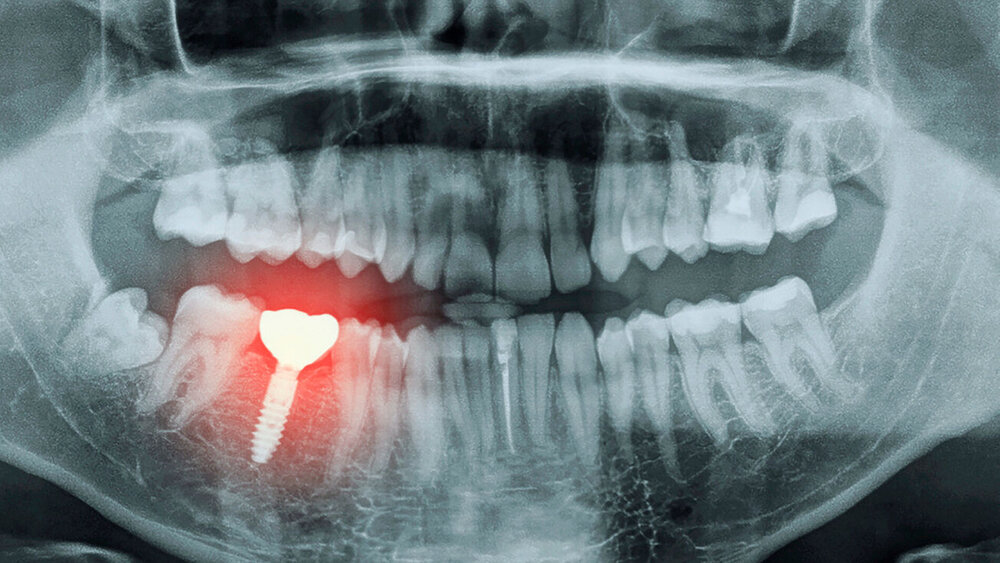

Von zahnmedizinischem Interesse sind dabei vor allem Effekte der SSRI auf die Speichel- und auf die Knochenbildung. Bei langfristiger Einnahme von SSRI-Antidepressiva erhöht sich beispielsweise das Risiko, Karies zu entwickeln, da die Anwendung häufig mit Mundtrockenheit verbunden ist. Das Fehlen von Speichel hat nachteilige Folgen für die Mundflora und beeinflusst auch die Wundheilung negativ. So ist das Einheilen von Implantaten durch die Mundtrockenheit ebenfalls erschwert.

Hier kommt noch ein weiterer Effekt der SSRI zum Tragen: Vorangegangene Studien deuten an, dass SSRI die Knochenbildung verringern und das Risiko für Knochenbrüche erhöhen. Auch die Osseointegration eines Implantats wird durch den Knochenstoffwechsel beeinflusst. Mehrere Studien haben einen Zusammenhang zwischen der Anwendung von SSRI und dem Risiko von Ausfällen bei osseointegrierten Implantaten hergestellt.